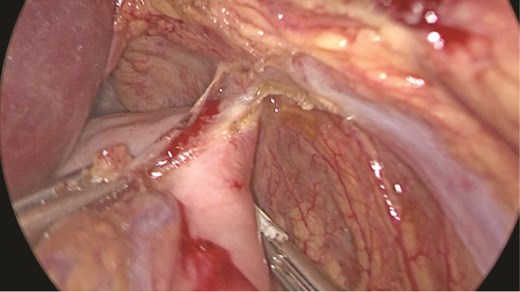

Multidisciplinary discussion was held to evaluate the most appropriate course of action for the patent condition, and the consensus was reached to pursue embolization as a first intervention. Embolization was performed by interventional radiology with no complications post-procedure, and the patient was optimized prior to her procedure. Patient was taken to the operating room in stable conditions. The spleen was enlarged around 20 cm. Inferiorly, the omentum and part of the transverse colon was attached to the spleen (Fig. 3), so we freed the omentum from the splenic tissue. The dissection continued until reaching short gastric vessels and entering the lesser sac (Fig. 4). Once the lesser sac was entered, the splenic vessels were identified (Figs 5 and 6), the splenic vein was hugely dilated with multiple collateral branching vessels at the hilum. Gaining posterior mobilization of the vein was challenging. The splenic artery was tortuous from the insertion around itself (Fig. 7). After complete mobilization of the fundus, we elected to divide each vessel starting with the splenic artery so we can achieve full mobilization of the vein (Fig. 9). After controlling the splenic artery, the splenic vein was dissected proximal to the splenic hilum (Fig. 8). It was hugely dilated and its wall is thickened secondary to AV fistula. It was difficult to achieve circumferential dissection, so we decided at that moment to convert to laparotomy to complete ligating the vein and to retrieve the specimen (Fig. 10a and b).

Anterior portion of the splenic vein seen posterior to the stomach.